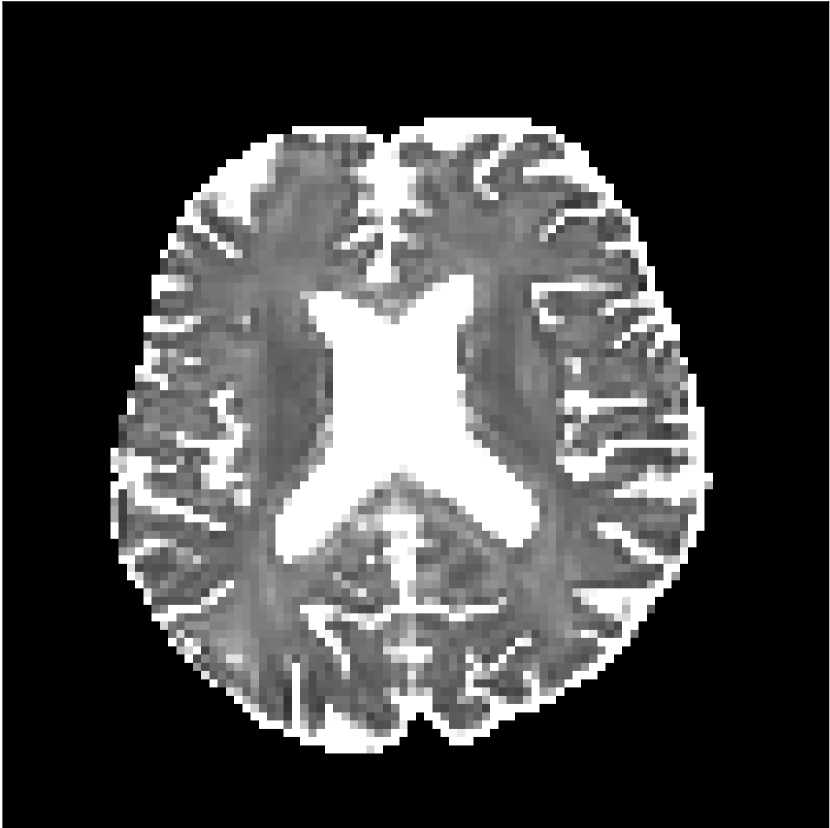

Figure 8 shows examples of non-diffusion-weighted images before and after processing. The raw images (Raw) served as the input for the magnitude deep learning (MCNN) and complex deep learning (CCNN) methods.

Raw 𝐱tsubscript𝐱𝑡\mathbf{x}_{t}

MCNN, fθ^(𝐱t)subscript𝑓^𝜃subscript𝐱𝑡f_{\hat{\theta}}\left(\mathbf{x}_{t}\right)

MCNN Resid., Ric(𝐱t)fθ^(𝐱t)Ricsubscript𝐱𝑡subscript𝑓^𝜃subscript𝐱𝑡\text{Ric}(\mathbf{x}_{t})-f_{\hat{\theta}}\left(\mathbf{x}_{t}\right)

CCNN, fθ^(𝐱t)subscript𝑓^𝜃subscript𝐱𝑡f_{\hat{\theta}}\left(\mathbf{x}_{t}\right)

CCNN Resid., Ric(𝐱t)fθ^(𝐱t)Ricsubscript𝐱𝑡subscript𝑓^𝜃subscript𝐱𝑡\text{Ric}(\mathbf{x}_{t})-f_{\hat{\theta}}\left(\mathbf{x}_{t}\right)

No PF

5/8 PF

Figure 8: Examples of non-diffusion-weighted images from in vivo data at b=0𝑏0b=0 s/mm2. Artifacts in the Raw image, 𝐱tsubscript𝐱𝑡\mathbf{x}_{t}, are corrected by the MCNN and CCNN models, fθ^(𝐱t)subscript𝑓^𝜃subscript𝐱𝑡f_{\hat{\theta}}(\mathbf{x}_{t}). Also shown are the residuals between the CNN corrections and the original Raw image with Rician bias correction Ric(𝐱t)Ricsubscript𝐱𝑡\text{Ric}(\mathbf{x}_{t}) [10]. The Gibbs artifacts removed by the methods are observed in the residuals. The MCNN method introduces some banding artifacts at the PF 5/8ths factor that are not present in the CCNN method.

Both methods remove artifacts, but the MCNN method allows residual rippling artifacts to pass through in the presence of partial Fourier. These rippling artifacts are not present in the CCNN method.